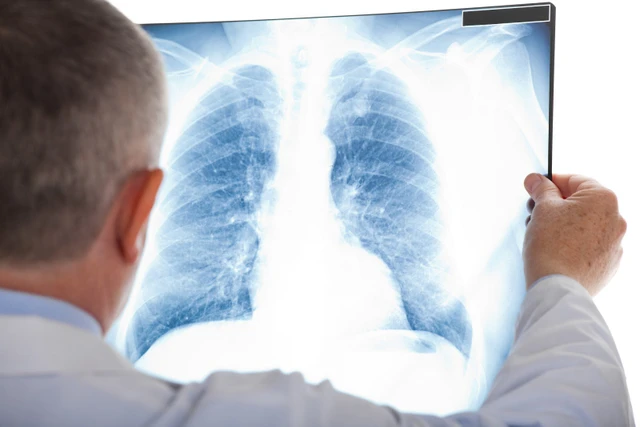

Tràn dịch màng phổi là một triệu chứng rất thường gặp với tỷ lệ mắc là như nhau ở cả nam và nữ. Tràn dịch màng phổi thường là do ảnh hưởng từ bệnh lý khác gây nên. Do vậy, khi có dấu hiệu của tràn dịch màng phổi, hãy liên hệ bác sĩ ngay để kịp thời can thiệp và có phương pháp điều trị phù hợp.